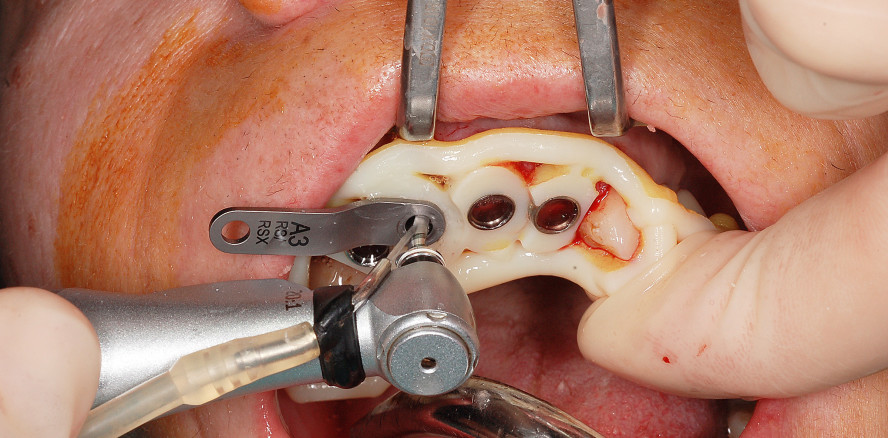

Der operative Eingriff erfolgte unter Lokalanästhesie (Artikamine 1:100.000, Adipharm SA, Athen). Zunächst wurden die fünf nicht erhaltungswürdigen Zähne 13–22 unter größtmöglicher Schonung des Alveolenknochens extrahiert (Abb. 9 und 10). Nach Bildung eines minimalinvasiven Mukoperiostlappens erfolgte die navigierte Präparation für die Implantate mit einem Bohrersatz (BEGO Guide; Abb. 11). Die Bohrschablone wurde auf den Restzähnen bzw. implantatprothetischen Rekonstruktionen befestigt und während der Präparation zusätzlich manuell abgestützt (Abb. 12). In Regio 13/12 sowie 22 wurden Implantate (BEGO Semados S) mit einem Durchmesser von 3,25 mm und einer Länge von 13 mm eingesetzt. In Regio 11 und 21 erfolgte die Implantatversorgung mit zwei Implantaten (BEGO Semados RS) mit einem Durchmesser von 3,75 mm und einer Länge von 13 mm (Abb. 13). Alle Implantate wurden ca. 1 mm subkrestal mit einem Torque von 40 Ncm primärstabil inseriert. Über einen Zeitraum von fünf Tagen erfolgte eine prophylaktische postoperative Antibiotikagabe (Augmentin 625 dreimal pro Tag). Als Schmerzmittel wurde Ibuprofen 400 mg verordnet, das bei Bedarf genommen werden sollte. Es traten keine postoperativen Beschwerden oder sonstige Komplikationen ein.